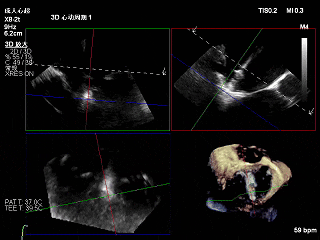

TEER术前评估

术前Bicom切面

术前X-Plane

术前瓣口面积5.39cm²

后叶长度9.24cm

可用房间隔穿刺高度4.03cm

3D-ZOOM 彩色多普勒显示反流主要来源于2区